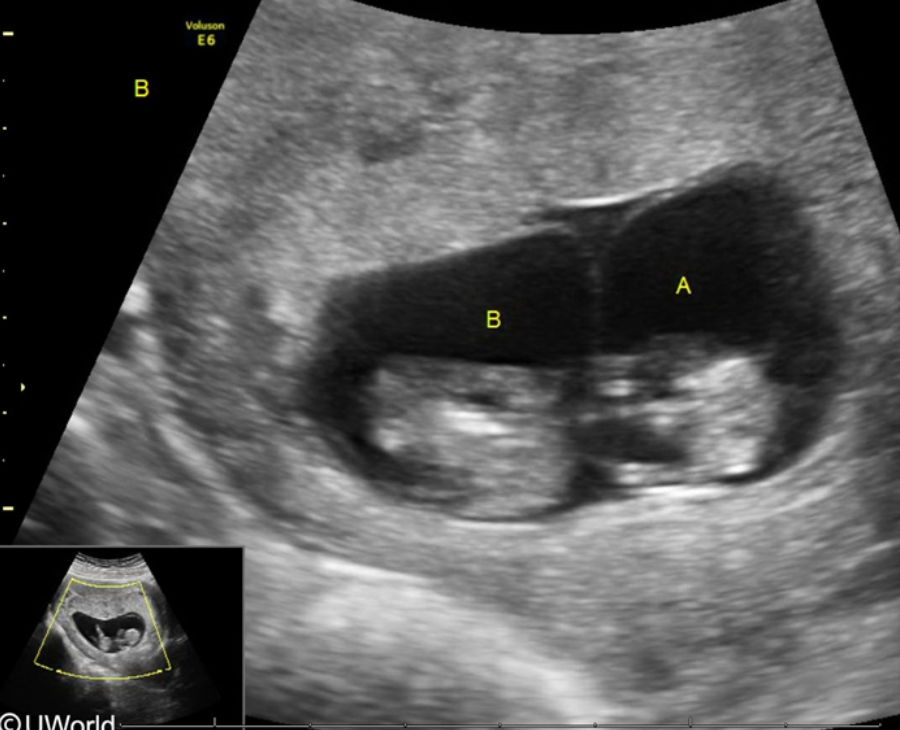

Monochorionic diamniotic twins (1 placenta, 2 amniotic sacs)

This pregnancy is at risk for what complication?

Monochorionic diamniotic twins are at risk for discordant fetal growth in the setting of twin-twin transfusion syndrome